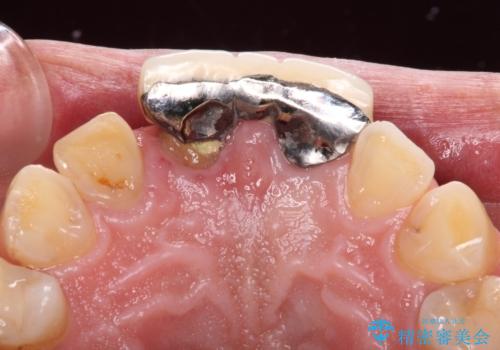

- 前歯の違和感と不自然な形態のブリッジを気にして来院された患者様です。

検査したところ、右前歯は抜歯が必要であったので、ブリッジを新製することとしました。

1歯は根管治療を行うことが必要と判断されたため、根管治療を実施することとしました。

歯肉移植や根管治療終了後、オールセラミッククラウンおよびブリッジにて補綴することとしました。